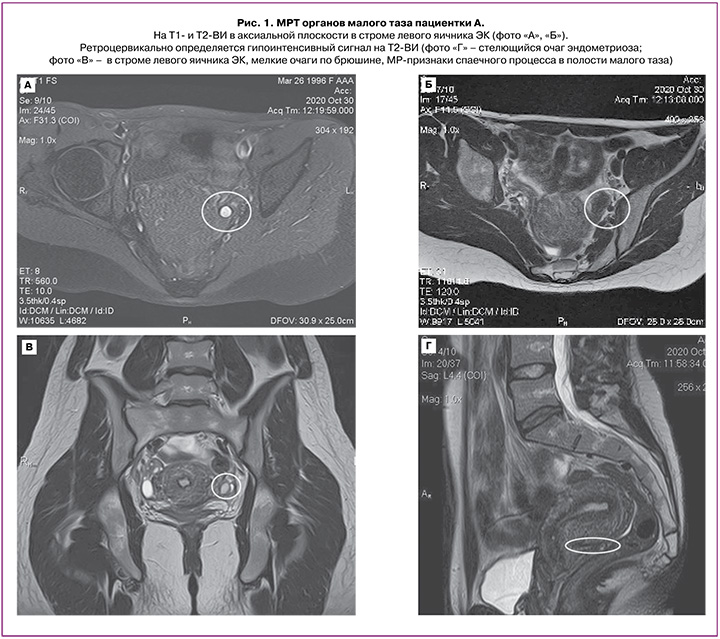

МРТ органов малого таза было выполнено в октябре 2020 г. специалистом экспертного уровня; был определен РЦ-очаг (1,7×0,8×0,6 см) эндометриоза (рис. 1Г) с преимущественным распространением в левые отделы, фиксацией левого яичника, ЭК левого яичника (1,2×0,5×0,9 см) (рис. 1А, В), МР-признаки эндометриоидных гетеротопий по брюшине таза, крестцово-маточных связок (КМС) на фоне спаечного процесса. МР-картина начальных признаков аденомиоза.